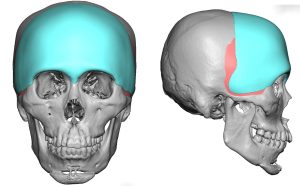

A: Thank you for your inquiry and your very articulate and intellectual description of your aesthetic head shape concerns, objectives and the aesthetic challenges that come with trying to rectify them all in a proportionate and harmonious manner. I will answer your questions in detail but have attached a few prior patient custom skull implant designs in the spirit of ‘a picture is worth a thousand words’ that have addressed similar patient concerns.

A: Thank you for your inquiry and your very articulate and intellectual description of your aesthetic head shape concerns, objectives and the aesthetic challenges that come with trying to rectify them all in a proportionate and harmonious manner. I will answer your questions in detail but have attached a few prior patient custom skull implant designs in the spirit of ‘a picture is worth a thousand words’ that have addressed similar patient concerns.

1) Any implant design that needs to go past the bony temporal line will sit on top of the temporalis fascia/muscle.

2) Depending upon how much the implant design crosses the temporal and how much forehead width and frontal augmentation is needed, the implant design may have to cover the anterior temporal region to prevent creating unaesthetic temporal hollowing.

3) In men you design as part of the implant a temporal line of transition between the forehead and the temporal area. (subtle raised ridge) In women this is not necessary.